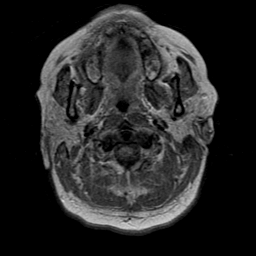

Cerebral hemorrhage, MR Study mr-pd -- Slice #1

[Home][Help][Clinical] Slice 1